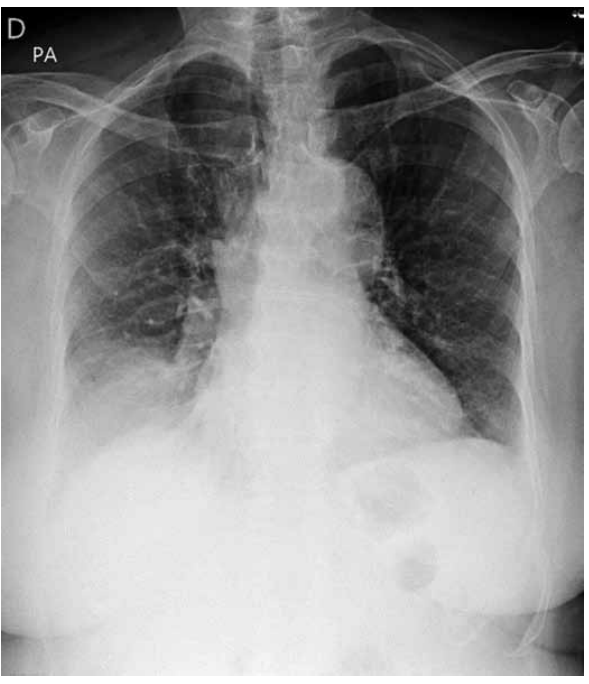

Analise a radiografia de tórax a seguir.

(Arquivo pessoal; imagem usada com autorização)

A radiografia apresenta a seguinte alteração compatível com o envelhecimento: